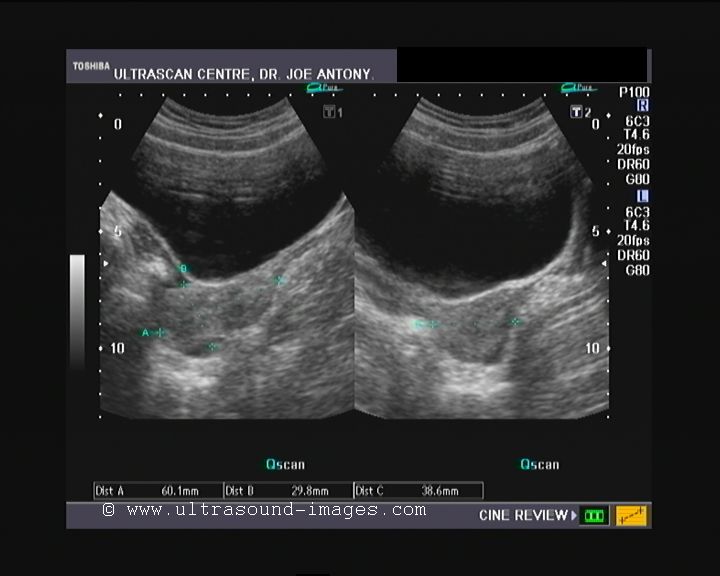

Visualizing PCOS String of Pearls Ultrasound Diagnosis Empowered String Of Pearls Uterus this creates problems with your ovaries: several imaging features are characteristic of adnexal torsion and can be seen to varying degrees across different modalities: You might have irregular periods or no periods, and you could get. The follicles might be scattered throughout the ovary or distributed. the “string of pearls” sign is shown in the inset images. String Of Pearls Uterus.

The Pelvic Ultrasound Scan Fertility Test Conception Advice String Of Pearls Uterus fdp is an essential feature of pcos. several imaging features are characteristic of adnexal torsion and can be seen to varying degrees across different modalities: You might have irregular periods or no periods, and you could get. this creates problems with your ovaries: The follicles might be scattered throughout the ovary or distributed. the “string of. String Of Pearls Uterus.

Ultrasound in Polycystic Ovarian Syndrome What? When? How? Why? Who String Of Pearls Uterus the “string of pearls” sign is shown in the inset images as “pearls” (white dots) on a “string” (curving white line). fdp is an essential feature of pcos. this creates problems with your ovaries: several imaging features are characteristic of adnexal torsion and can be seen to varying degrees across different modalities: The follicles might be. String Of Pearls Uterus.